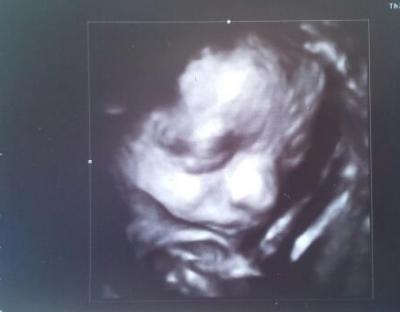

Hallo die ihr Lieben! Bin zurück vom FA, wo eigentlich auch die Herztöne hätten abgehört werden sollen... Aber die Kleine war nicht kooperativ und man hörte nur immer für max. 30 Sekunden zwischendurch mal etwas. Hoffe, dass es nächstes Mal besser wird (in 3 Wochen). Sie wiegt ca. 1.500 gr, ist munter und Kopf liegt unten. An der Grenze: meine Gewichtszunahme (11 Kilo....) und dass ich viel Fruchtwasser habe - an der oberen Normgrenze. Mein Bauchumfang kurz unter dem Nabel ist jetzt 105 cm. Habe mal ein Foto meiner Maus angehängt. Dunkle Haare und die Denkerhand links oben am Kopf . Total süß - ich bin so stolz und glücklich! Wahnsinn. Keine Anzeichen von SS-Depression. Mein Zuckerbelastungstest war super - keine Besonderheiten. Leider leide ich noch immer unter bakteriellen Vaginalinfektionen und Blasenentzündung, die ich wohl bis zum Ende nicht mehr ganz in den Griff bekommen werde, wie mein Arzt meint. Hauptsache der Kleinen gehts gut! Alles Gute auch weiterhin für euch! Bin gespannt auf eure Daten (Bauchumfang, Gewichtszunahme, Kindsgewicht,...) Liebe Grüße, Neffi

Bild zu Zurück vom FA und BILD :-) - Forum für April - Mamis

Hallo Schön das alles soweit in Ordnung ist. Ist das ein schönes Bild will auch! GLG Tanja

sooooo eine zuckerpüppi

sehr süß das bild>! schön das alles gut ist mit der maus...doof das die entzündungen immer noch nich weg gehen wollen!

Wirklich süßes Bild. An Daten habe ich leider keine... Muss das nächste Mal genau nachfragen. Bin allerdings erst in 3 Wochen wieder dran. LG

Hallo Neffi, Total süßes Bildchen! Super, dass bis auf die Infektion und die Entzündung (drück die Daumen, dass bald alles wieder okay ist) alles bestens ist! Letzten Mittwoch hatte mein Kleiner ca.1300g. Am Montag hab ich einen Termin zur FD und bin schon gespannt, was er in den zwei Wochen zugelegt hat! Zugenommen hab ich noch nichts, bin immer noch unter dem Ausgangsgewicht.... Mein Bauchumfang liegt bei knapp 130....hatte allerdings auch schon einen großen Bauchumfang am Anfang der Schwangerschaft! Was heißt das mit dem Fruchtwasser bei dir....kannst du da was beeinflussen? Liebe Grüße Sonja